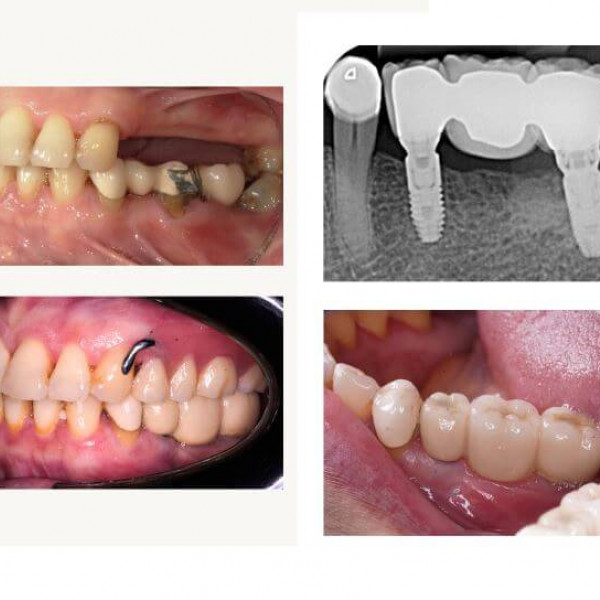

Galeri